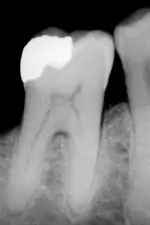

An X-ray showing enamel and dentin replaced by an amalgam restoration

Most dental restorations involve the removal of enamel. Frequently, the purpose of removal is to gain access to the underlying decay in the dentin or inflammation in the pulp. This is typically the case in amalgam restorations and endodontic treatment.